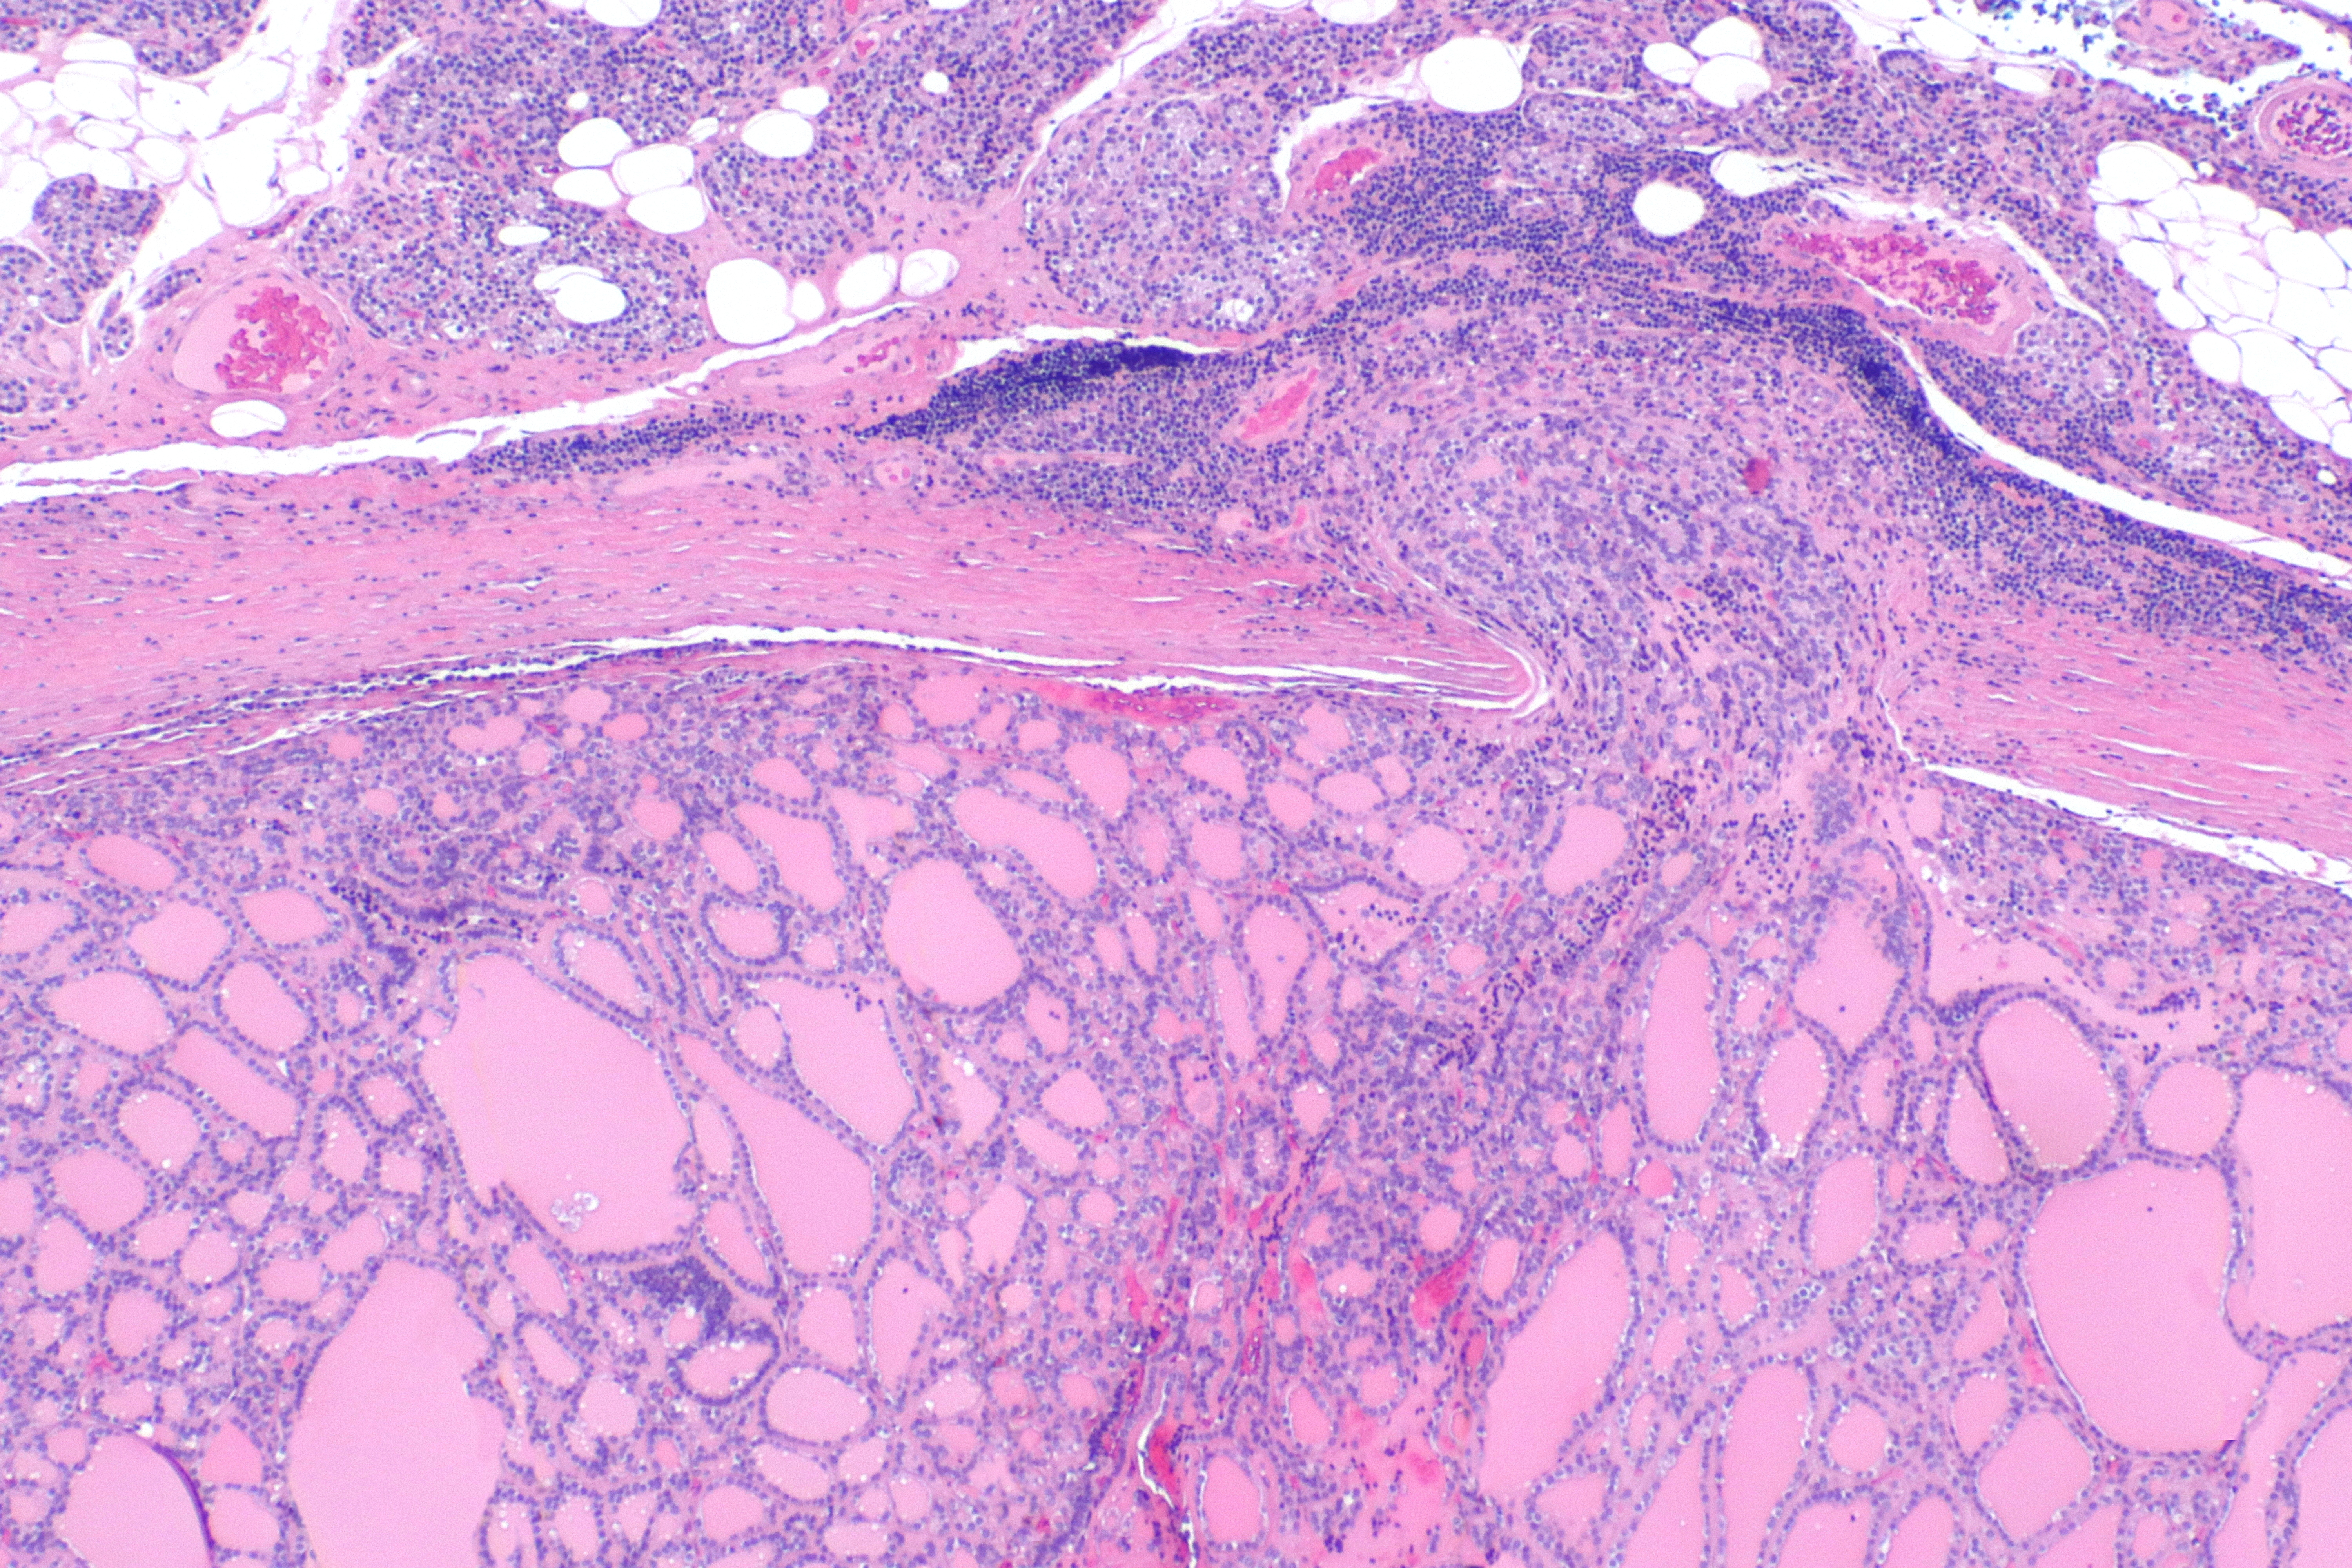

갑상선 여포종양(Follicular neoplasm): 말그대로 신생물이기 때문에, "benign follicular adenoma"와 "follicular carcinoma"을 포함하는 개념

- FA(follicular adenoma)와 FTC(Follicular caricnoma)둘다 follicular cell의 분화로 생기고, 현미경적으로 미여포세포(micro-follicular architecture)을 가져서, follicle이 엄청 작은 형태로 있는 것

FA(follicular adenoma)은 양성종양으로 갑상선에 섬유성 피막(fibrous capsule)내에 둘러쌓여있는 종양

FTC(Follicular caricnoma): 악성종양.

- 현미경적 특징:

- FA와 유사하지만, 두껍고 불규칙한 캡슐, 괴사(necrosis), 세포분열(mitosis) 많음

- 피막 침범: capsule 전체를 완전히 뚫고 지나가는 경우에 한해, 캡슐 두께가 a인데, a만큼 다 못뚫엇다면 FA에 해당

- 혈관침범: 혈관의 캡슐 내,외강 모두 가능.